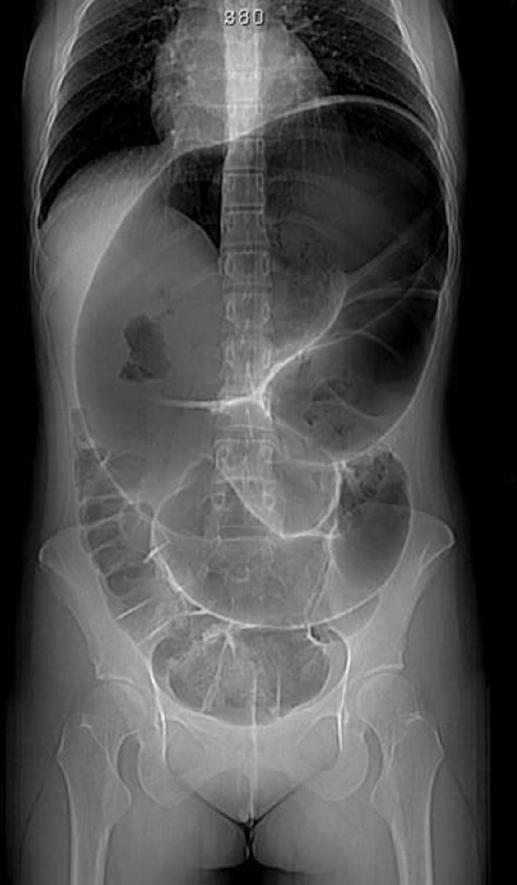

Se realizan estudios de laboratorio, incluyendo biometría hemática completa, pruebas de función renal y hepática, electrolitos séricos, tiempos de coagulación y gasometría arterial, reportándose leucocitosis con neutrofilia (23 × 103/μl, 90% neutrófilos), así como datos de acidosis metabólica y lesión renal aguda incipiente. Una radiografía de abdomen en bipedestación a su ingreso muestra importante dilatación del colon, de hasta 20 cm en su diámetro máximo, con imagen en «grano de café» (Fig. 1). Se realiza tomografía computarizada de abdomen y pelvis, la cual constata una importante dilatación del colon transverso, descendente y sigmoides, con alteraciones del mesenterio (Fig. 2).

Figura 1 Radiografía simple de abdomen en bipedestación, de proyección anteroposterior, en la cual se observa la imagen típica en «grano de café», con dilatación significativa del intestino involucrado, así como ausencia de gas en ámpula rectal.